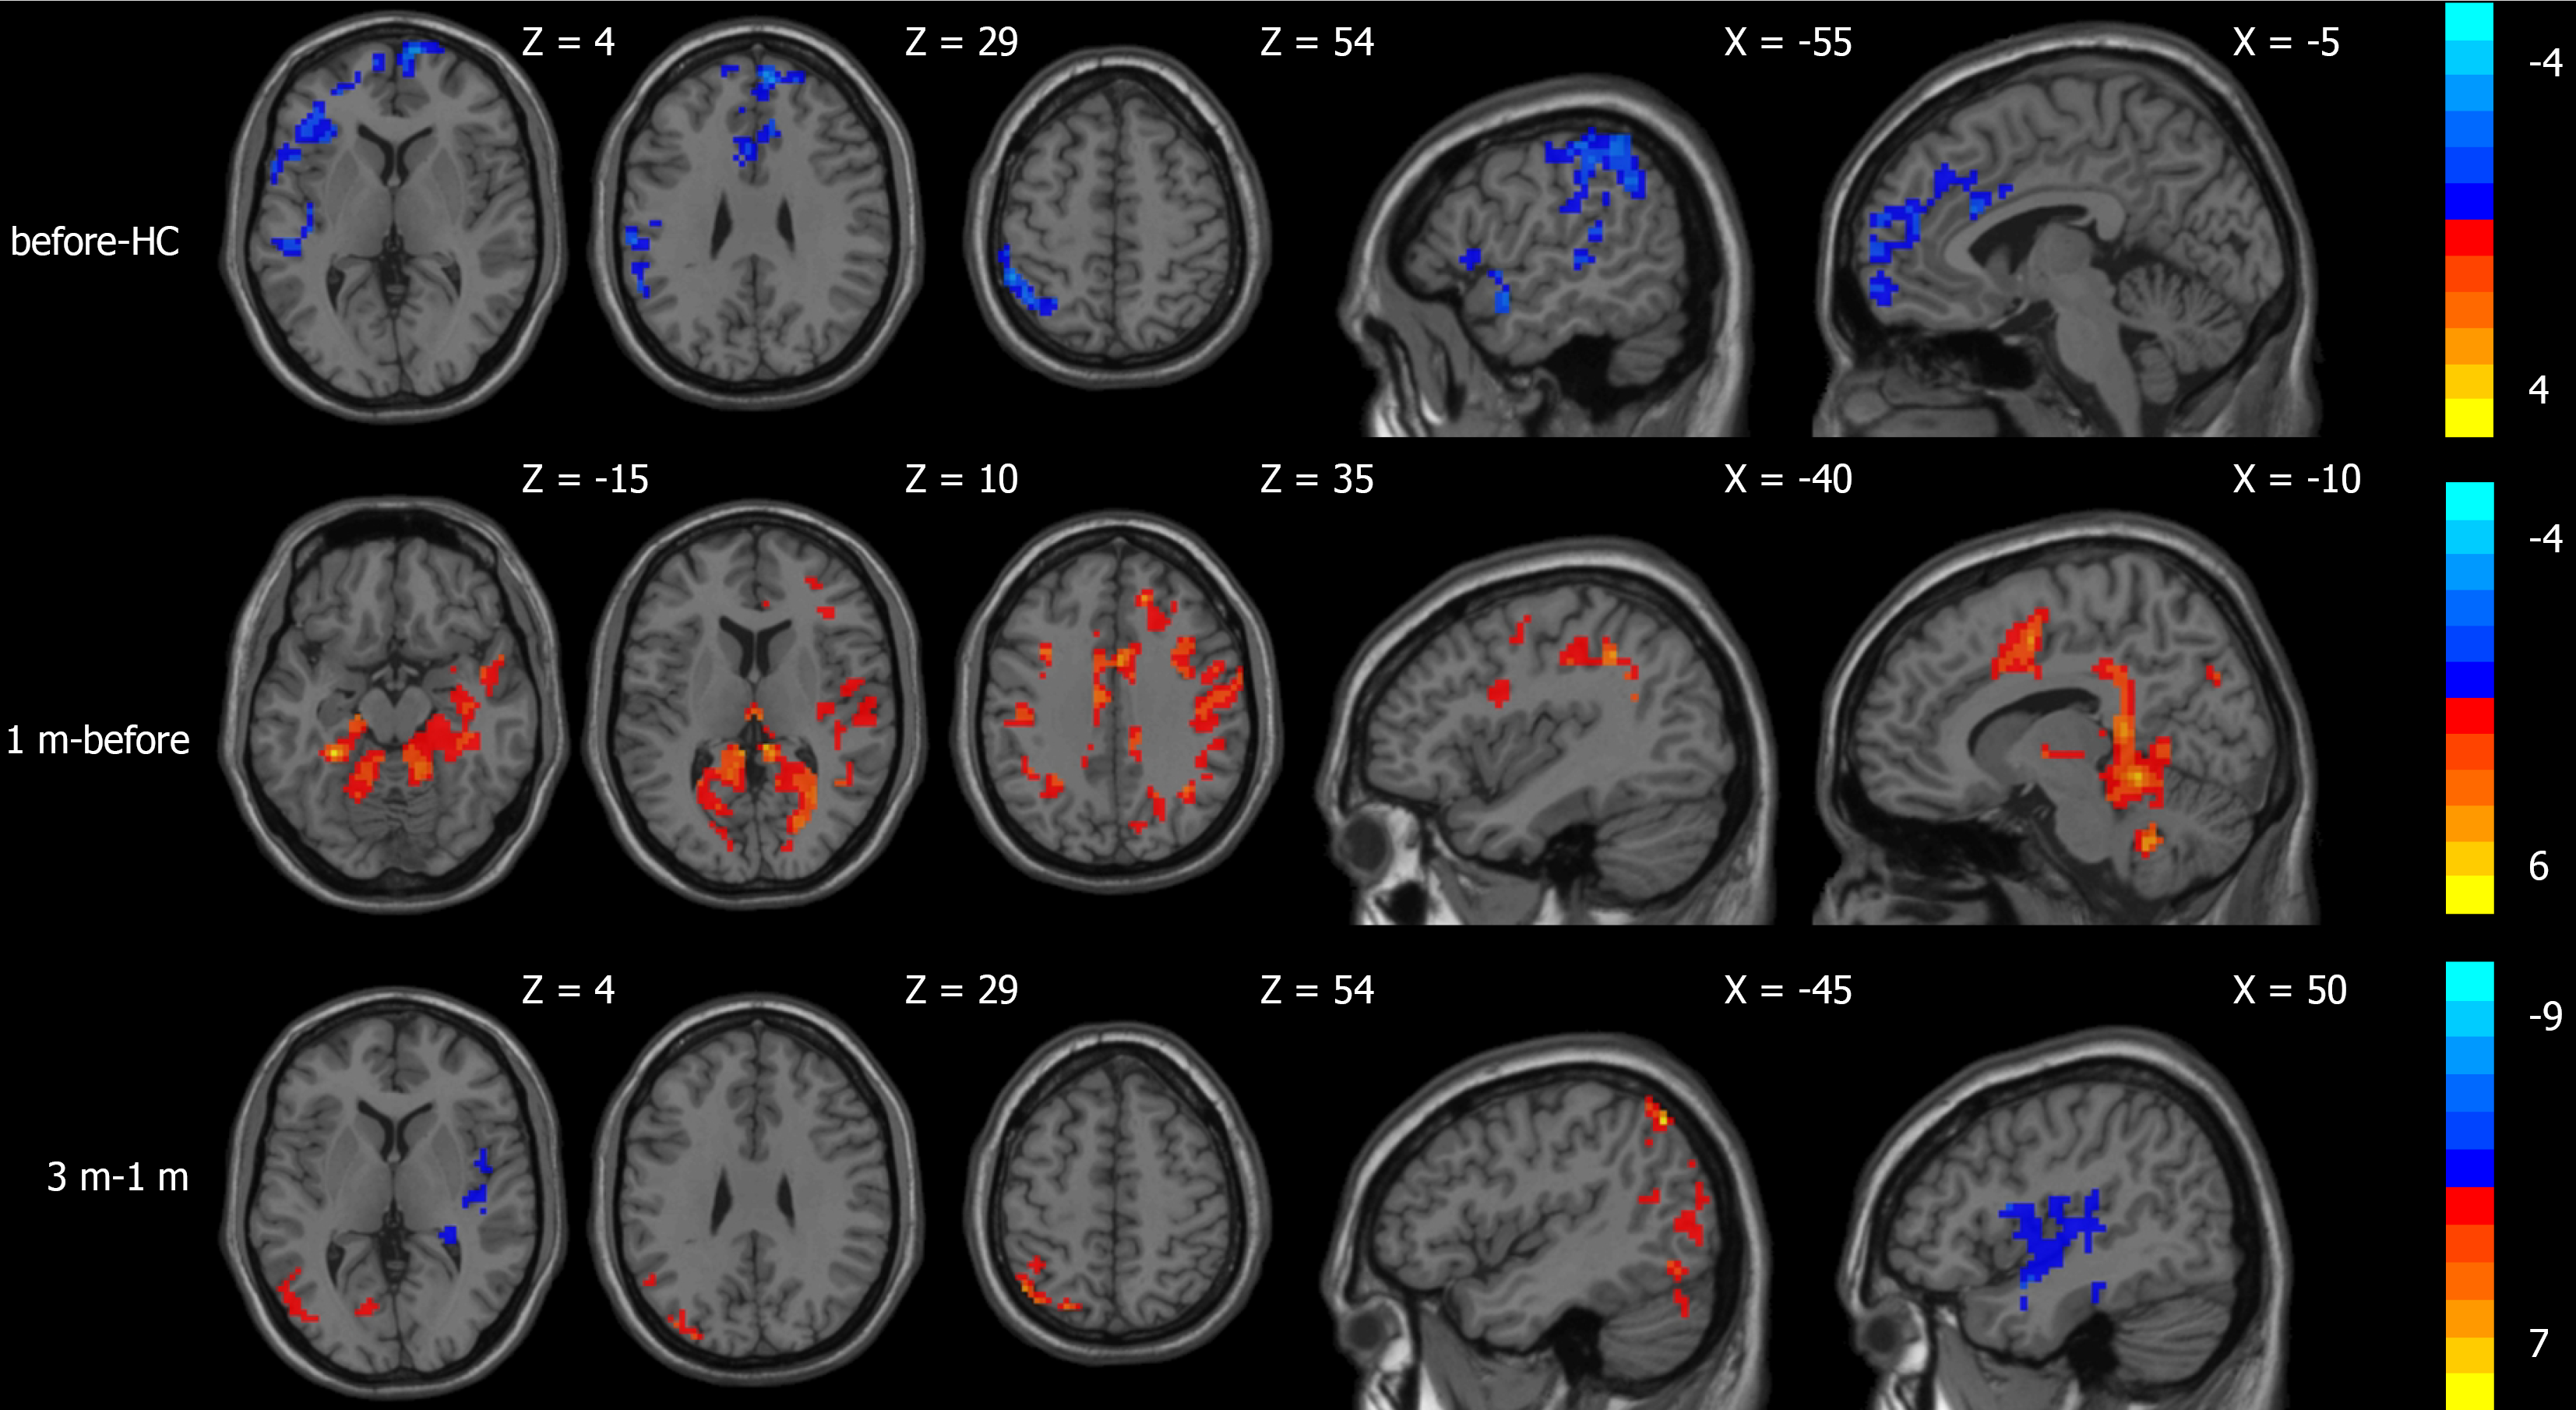

Compared to the normal control group, the CBF values of patients with portal hypertension and cirrhosis decreased in the area centered on the right orbitofrontal gyrus and the left superior temporal gyrus. The ALFF values decreased in the area centered on the left superior temporal gyrus, the left inferior frontal gyrus of the operculum, and the right precuneus. Compared to before TIPS, the CBF values increased in the area centered on the left fusiform gyrus 1 month after TIPS. The ALFF values increased in the area centered on the left superior temporal gyrus; there were no areas with significant CBF differences 3 months after TIPS. The ALFF values increased in the area centered on the left orbitofrontal gyrus and the left precuneus 3 months after TIPS. In comparison to 1 month after TIPS, CBF values decreased in the area centered on the right fusiform gyrus and increased in the area centered on the left angular gyrus 3 months after TIPS. ALFF values decreased in the area centered on the right insula and the cerebellum (Table 2; Figures 2 and 3).

| Group | Brain regions | MNI coordinates (mm) | Volume (mm3) | Peak (t-value) | ||

| X | Y | Z | ||||

| Comparison results of CBF differences | ||||||

| Before-HC | R. orbitofrontal superior gyrus | 9 | 66 | -12 | 1056 | -4.62 |

| L. superior temporal gyrus | -60 | -27 | 18 | 537 | -3.96 | |

| 1 m-before | L. fusiform gyrus | -30 | -39 | -18 | 5280 | +6.56 |

| 3 m-1 m | R. fusiform gyrus | 39 | -33 | -21 | 512 | -4.39 |

| L. angular gyrus | -45 | -63 | 51 | 587 | +7.93 | |

| Comparison results of ALFF differences | ||||||

| Before-HC | L. superior temporal gyrus | -39 | -33 | 12 | 1502 | -6.68 |

| L. opercular part of inferior frontal gyrus | -48 | 9 | 21 | 213 | -6.36 | |

| R. precuneus | 15 | -60 | 21 | 3765 | -6.04 | |

| 1 m-before | L. superior temporal gyrus | -48 | -30 | 21 | 687 | +4.68 |

| 3 m-before | L. orbitofrontal superior gyrus | -6 | 51 | -6 | 298 | +5.95 |

| L. precuneus | -3 | -75 | 51 | 458 | +7.69 | |

| 3 m-1 m | R. insula | 36 | -27 | 18 | 513 | -6.43 |

| Cerebelum_Crus1_L | -24 | -72 | -33 | 851 | -6.64 | |